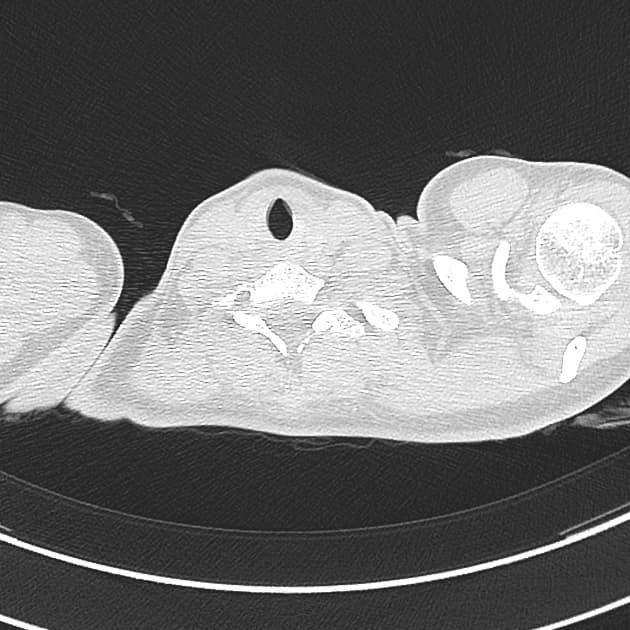

Theo dõi sau 8 tháng

Chất lượng hình ảnh: một số artefact, không có hạn chế khác

Phân tích chức năng: không có thay đổi đáng kể so với lần khám trước

- Rối loạn chức năng tâm trương với giãn thất bất thường trên quan sát trực tiếp

- Thành cơ tim thất trái và thất phải, vách liên nhĩ và thành tâm nhĩ phải vẫn dày nhẹ

- Tràn dịch màng ngoài tim mức độ nhẹ và tràn dịch màng phổi nhỏ, nhưng ít hơn so với lần trước

Đặc tính mô cơ tim:

- STIR: tín hiệu tăng lan tỏa ở cơ tim, đặc biệt ở các đoạn vách và mặt dưới

- Look-Locker: cơ tim được triệt tiêu trước buồng máu như lần trước (và như mong đợi)

- PSIR: buồng máu tối và bắt thuốc muộn bằng gadolinium lan tỏa, dưới nội tâm mạc

- Bản đồ T1 tự nhiên: 1100–1160 ms (z-score: 3–5)

- Thể tích ngoại bào (ECV): 40–50%

- Bản đồ T2: 56–60 ms (z-score: 2–3)

- Xơ cứng tinh thể AL đang điều trị

- Chức năng tâm thu hạn chế nhẹ và rối loạn giãn tâm thất

- Giá trị T1 tự nhiên, T2 và thể tích ngoại bào bất thường như dự kiến, nhưng có cải thiện nhẹ so với lần khám trước trong quá trình điều trị

Khám theo dõi sau 8 tháng cho thấy cải thiện nhẹ các giá trị T1, T2 bất thường và thể tích ngoại bào dưới điều trị.